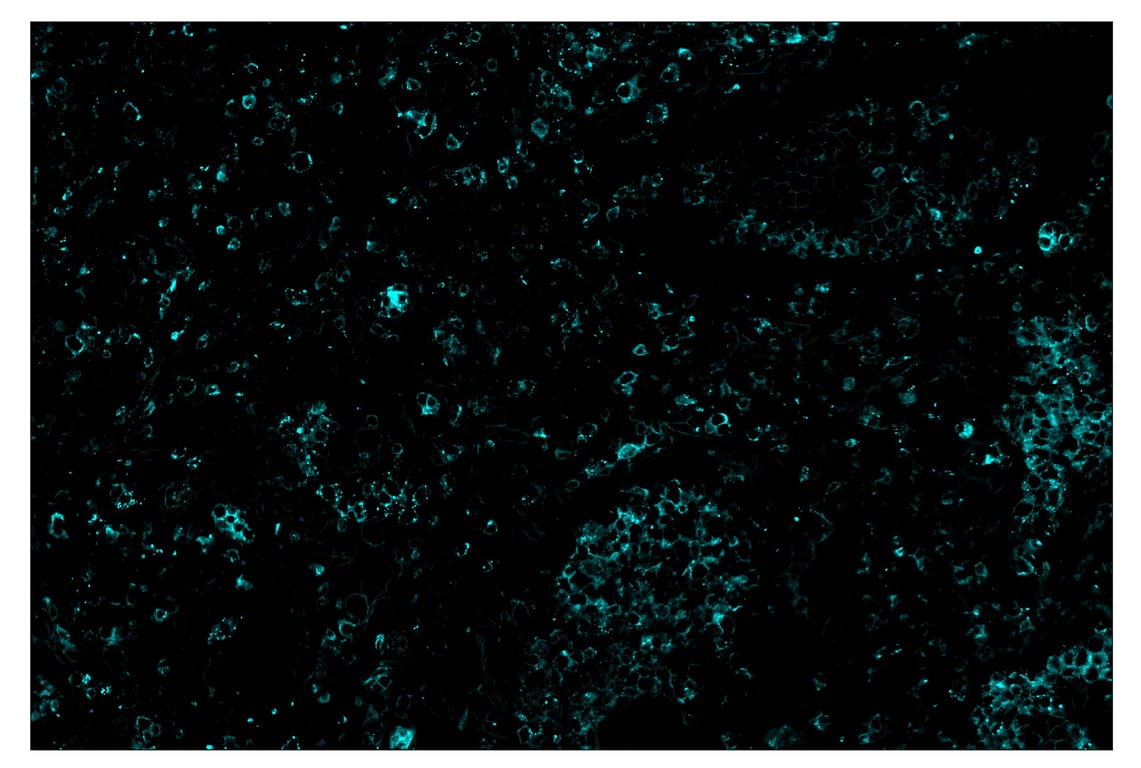

SignalStar™ immunohistochemical analysis of paraffin-embedded human non-small cell lung carcinoma using TIM-3 (D5D5R™) & CO-0010-750 SignalStar™ Oligo-Antibody Pair #34802 (cyan). All fluorophores have been assigned a pseudocolor, as indicated. Staining was performed on the BOND RX by Leica Biosystems.

Immunohistochemistry Image 5: TIM-3 (D5D5R<sup>™</sup>) & CO-00010-488 SignalStar<sup>™</sup> Oligo-Antibody Pair